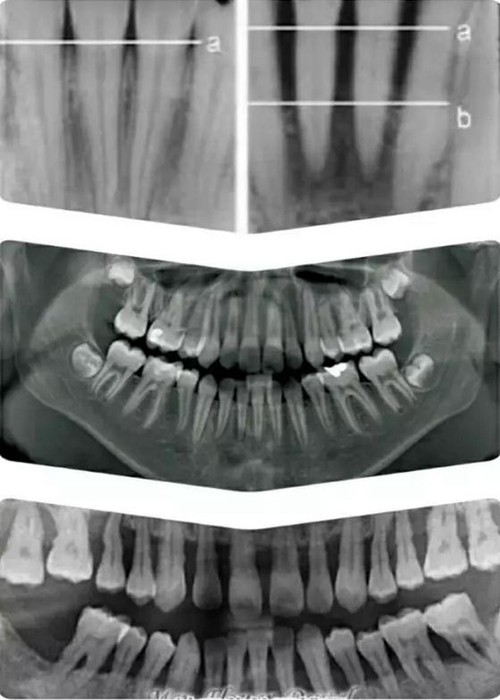

如上圖所示。 牙周這個詞或許有點陌生,它指的是牙齒周圍,包埋著牙根的硬質的牙槽骨,和覆蓋其上肉眼可見的粉色牙齦。

牙槽骨對牙齒起主要固定支撐作用,并且一般只能在X 光片上顯示;牙齦是保護牙槽骨的第一道屏障。

有圖有真相。上面這組圖片,自上而下從左至右,顯示了人類健康牙齒,患牙周病后,未加治療控制,以致病況越來越嚴重,最終牙齒逐漸脫落的過程。

牙周病也稱牙周炎,是包繞牙齒周圍的牙齦和牙槽骨因發(fā)生炎癥而萎縮,對牙齒逐漸失去固定支撐作用以致牙齒逐漸松脫的一類最常見牙齒疾病。

在上圖X光顯示下,牙槽骨從正常水平 a 線萎縮到了b 線(中圖為正常全口X光牙片,最下圖為全口重度牙周病X光片),以至不能再固定支撐牙齒,就象埋在電線桿周圍的土被挖掉,電線桿只能逐漸倒伏一樣。